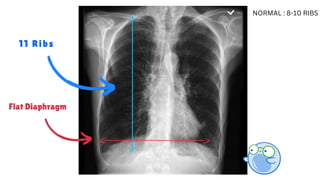

11 Ribs

Flat Diaphragm

NORMAL : 8-10 RIBS